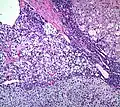

Histopathology

The microscopic histopathology analysis of the tissue samples obtained from the adrenal cortex of individuals presenting with adenoma-associated symptoms such as primary aldestronism (PA) indicates that adenoma cells are relatively larger with different cytoplasm, and increased variation in nuclear size. This indication is based on comparison between the healthy (normal) and affected (adenoma-associated) adrenal cortex tissue samples.

Adrenocortical adenoma with focal high grade nuclear atypia

Adrenocortical adenoma with focal necrosis